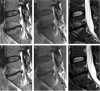

Materials and methods: A total of 180 patients were randomised to receive 100 days of amoxicillin or placebo. MC edema was assessed on MRI at baseline and one-year follow-up. Per-protocol analyses were conducted in subgroups with MC edema on short tau inversion recovery (STIR) or T1/T2-weighted MRI at baseline. MC edema reductions (yes/no) in STIR and T1/T2 series were analyzed separately. The effect of amoxicillin in reducing MC edema was analyzed using logistic regression adjusted for prior disk surgery. To assess the effect of amoxicillin versus placebo within the group with the most abundant MC edema on STIR at baseline ("STIR3" group), we added age, STIR3 (yes/no), and STIR3×treatment group (interaction term) as independent variables and compared the marginal means (probabilities of edema reduction).

Results: Compared to placebo, amoxicillin did not reduce MC edema on STIR (volume/intensity) in the total sample with edema on STIR at baseline (odds ratio 1.0, 95% CI: 0.5, 2.0; n=141) or within the STIR3 group (probability of edema reduction 0.69, 95% CI: 0.47, 0.92 with amoxicillin and 0.61, 95% CI: 0.43, 0.80 with placebo; n=41). Compared with placebo, amoxicillin did not reduce MC edema in T1/T2 series (volume of the type 1 part of MCs) (odds ratio: 1.0, 95% CI: 0.5, 2.3, n=104). Edema declined in >50% of patients in both treatment groups.